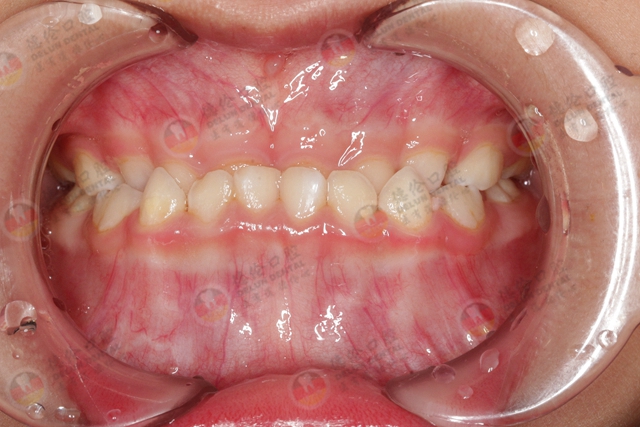

牙齿不齐,医学上称为错颌畸形,有的父母可能认为换牙期的牙齿不齐很正常,等换完牙就好了,可实际情况往往是,牙齿不齐大多数却只会越来越严重。

孩子的牙齿为什么容易长歪?

对于孩子来说,恒乳牙交替障碍(如乳牙滞留、乳牙早失等)是造成牙齿拥挤、长歪的重要原因。

2.过于精细化饮食

精细化饮食是导致青少年的错𬌗畸形的主要原因之一。现在的孩子饮食偏于精细,牙齿咀嚼食物的机会严重不足,进而对颌骨的刺激不够,导致颌骨发育不足。而恒牙数量没有减少而且体积比乳牙大很多,结果就导致牙量大于骨量,会出现牙齿排列不齐的情况。

3.长期不良口腔习惯

长期不良的口腔习惯同样是造成儿童牙齿畸形的原因之一。比如长期口呼吸可导致孩子上门牙突出,上唇变短。长期吮指可能导致开𬌗,上下牙闭合异常。

4.长期偏侧咀嚼

常用一侧咀嚼(偏侧咀嚼)会导致颜面发育异常,两侧脸型发育不对称。而不良的喂奶姿势会形成上牙反𬌗,也就是俗称的地包天。所以爸爸妈妈们不要让婴幼儿仰卧并自己手持奶瓶吃奶,因为奶瓶长期压迫上颌骨会限制其发育。